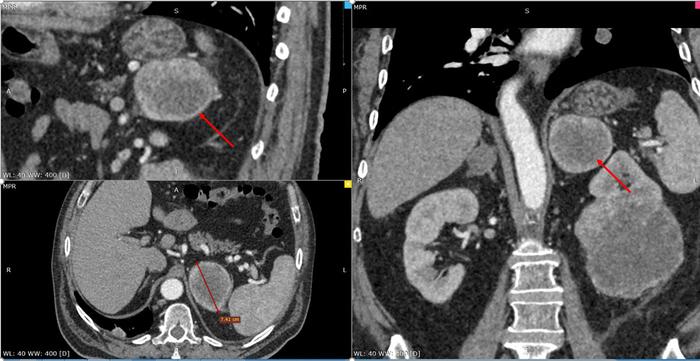

В практике врачей могут встречаться сложные случаи, например, когда у пациента была обнаружена опухоль размером 95 мм и метастаз в надпочечник размером 72 мм. Оба образования были успешно удалены с помощью лапароскопической техники.

Следующий аспект диагностики – многослойная компьютерная томография (МСКТ), которая является важнейшим этапом исследования.

С помощью МСКТ врачи получают полную картину:

- размер новообразования;

- расположение в тканей почки;

- наличие инвазий в сосуды или окружающие структуры;

- наличие тромбов, связанных с опухолью;

- метастазы в близлежащие лимфоузлы или надпочечник.